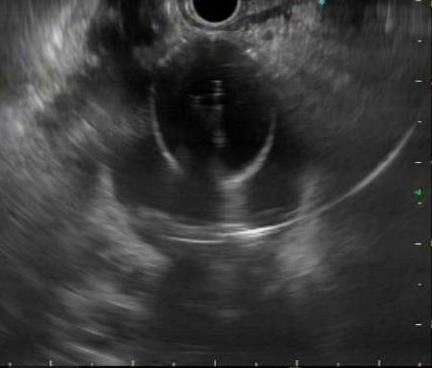

• 超声内镜引导下胃旁曲张静脉精准断流术治疗食管胃静脉曲张出血的疗效分析(附20例报告)

2025, 31(8):85-90. DOI: 10.12235/E20250036

摘要 (153) HTML (42) PDF 5.38 M (98) 评论 (0) 收藏

摘要:目的 探讨超声内镜引导下胃旁曲张静脉精准断流术治疗食管胃静脉曲张出血的疗效。方法 回顾性分析2024年1月1日-2024年12月31日于该院接受超声内镜引导下胃旁曲张静脉精准断流术治疗的20例肝硬化食管胃静脉曲张出血患者的临床资料,并评估治疗效果。结果 20例患者均顺利完成超声内镜引导下胃旁曲张静脉精准断流术;注射组织胶联合置入弹簧圈(16例)和单独注射组织胶(4例)均成功阻断胃旁来源的曲张静脉;所有患者均未发生穿孔、食管贲门狭窄、大出血、败血症和异位栓塞。1例单独注射组织胶的患者,术后胃旁曲张静脉少许渗血,经降低门静脉压力治疗3 d后好转,另1例单独注射组织胶患者,术后出现低热,抗感染3 d后体温恢复正常。结论 超声内镜引导下胃旁曲张静脉精准断流术治疗食管胃静脉曲张出血的临床疗效好,异位栓塞、大出血、感染和穿孔等并发症少,但仍需要密切随访,观察胃旁曲张静脉的排胶问题。